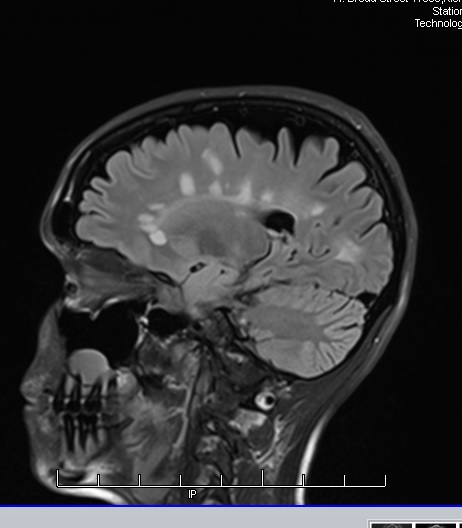

I choose not to believe it when I see it – instead, I’ll believe it fully within myself and then it will show itself. Every monumental and important concept was first imagined before it became a reality (ie, the light bulb!); I apply the same principle to my health. If I truly believe in something, it has the tendency to come to fruition, using my most recent MRI results as an example.